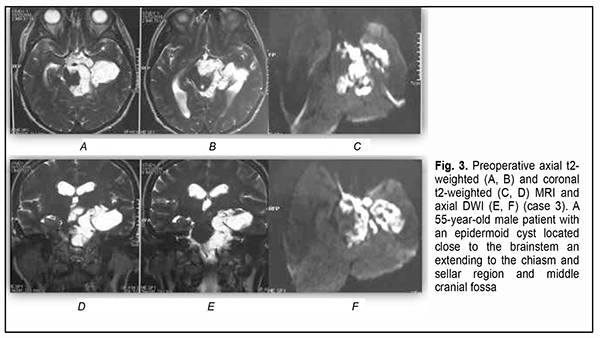

Introduction Epidermoid cysts manifest themselves clinically predominantly between the ages of 20 and 50 years, most commonly occur in the skull base, and usually arise in the subarachnoid cisterns, cerebellopontine angle and parasellar region. They grow slowly and can attain a large size before the onset of neurological symptoms. As the neoplasm grows, it gradually presses on, displaces and envelops the cranial nerves (CN) and adjacent vessels, and frequently invaginates the brainstem, causing ophthalmological abnormalities and lesions of relevant CN (Fig.1, 2, 3) [1, 2, 3].

Of the 21 patients, 7 (33.33%) had a gross total removal and 2 (9.53%) had a near total removal of the cyst, with residual capsule fragments not exceeding 2-3 mm (Figs. 4, 5, 6, and 7). In addition, 12 (57.14%) had a subtotal removal of the cyst, with either intraoperative evidence of residual capsule fragments measuring from 2 mm to 10 mm, or postoperative MRI evidence of residual capsule fragments not exceeding 11 mm in the largest dimension. The capsule adhesion to surrounding neurocascular structure at the location where the dissection was difficult was seen in 18 patients (85.7%). In some cases, this can lead to the impossibility of safe total capsule dissection from the brainstem and cranial nerves. Postoperative follow-up ranged from 1 to 12 years, with mean and median values of 38.5 ± 4.8 months and 24 months, respectively (Fig. 8).